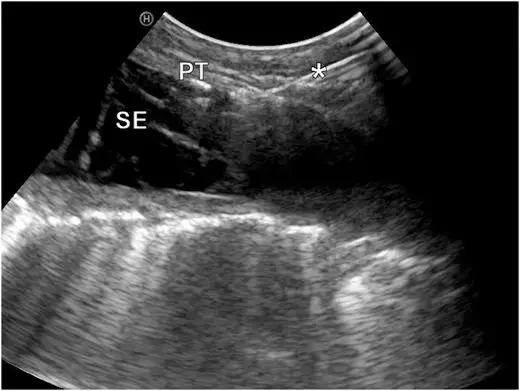

这是在彩超引导下的胸膜活检,胸水较少,胸膜局灶增厚。在穿刺中,可以看到针的所在位置。